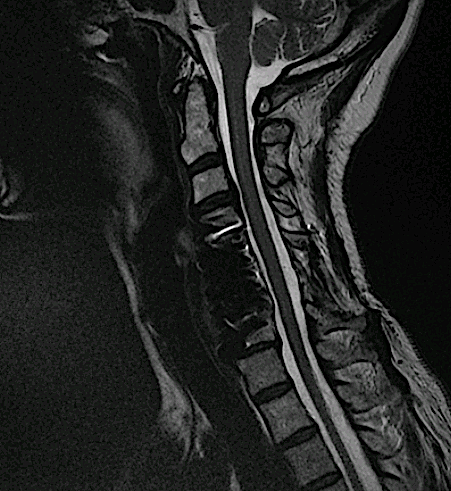

En ocasiones se presenta en la consulta algún paciente intervenido de una artrodesis anterior larga con una placa cervical que ha desarrollado un nivel adyacente (afectación de disco vecino). En el planteamiento de la solución quirúrgica se valora el abordaje a seguir:

Artrodesis cervical de más de 15 años de evolución en otro centro.

Dolor cervical alto con irradiación C3 refractario a tto médico